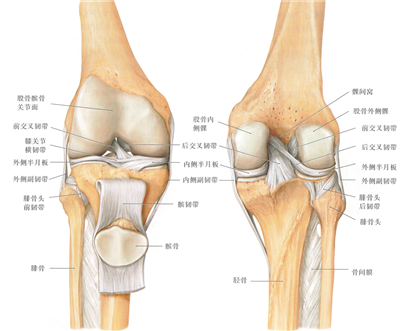

人体的膝关节内部构造什么样?

人类膝关节的解剖结构比较复杂,由股骨、胫骨、髌骨及围绕在它们周围的肌肉、韧带、软组织构成,膝关节一共分为三个间室,即内侧间室、外侧间室和髌股间室,围绕着三个间室有着三个重要的运动轴线,即胫股关节屈曲轴、髌股关节运动轴、膝关节旋转轴,这些运动的稳定主要依靠膝关节周围韧带参与,其中比较重要的有3组:

内外侧间室的中间有两条韧带,即前交叉韧带(ACL)和后交叉韧带(PCL),它们是膝关节屈伸及旋转活动时的重要稳定结构;

内侧间室的内侧和外侧间室的外侧也各有一条韧带,即内侧副韧带(MCL)和外侧副韧带(LCL),它们是膝关节旋转和内外翻活动时的重要稳定结构。

前方的髌骨由上方的股四头肌和下方的髌韧带固定,在股骨滑车上活动,是膝关节屈伸活动时的重要稳定结构。

人类膝关节内部构造和“三个间室”